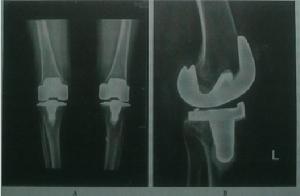

2.膝關節情況評估:膝關節畸形程度,軟組織平衡狀況,局部骨質狀況等。

3.人工膝關節術後位置評價。